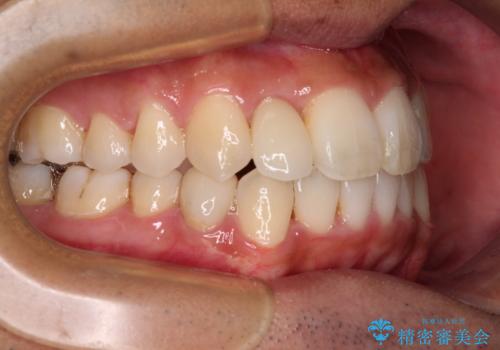

下顎の歯列弓に対して上顎歯列弓がやや小さく、側方の歯を中心にクロスバイトが見受けられました。

クロスバイトの改善は、インビザラインの場合歯髄壊死のリスクや咬み合わせが改善しきらないリスクがあるため、ワイヤー矯正をお勧めすることが多いですが、患者様の希望によりインビザラインにて矯正治療を行うこととしました。

後方に隠れていた上顎前歯は矮小歯であるため、矯正治療の途中でオールセラミッククラウンを装着し、左右対称の大きさでの仕上がりを目指すこととしました。